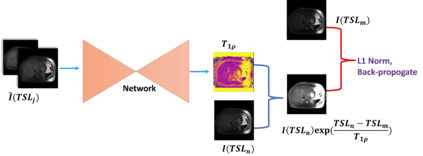

$T_{1\rho}$ mapping is a promising quantitative MRI technique for the non-invasive assessment of tissue properties. Learning-based approaches can map $T_{1\rho}$ from a reduced number of $T_{1\rho}$ weighted images, but requires significant amounts of high quality training data. Moreover, existing methods do not provide the confidence level of the $T_{1\rho}$ estimation. To address these problems, we proposed a self-supervised learning neural network that learns a $T_{1\rho}$ mapping using the relaxation constraint in the learning process. Epistemic uncertainty and aleatoric uncertainty are modelled for the $T_{1\rho}$ quantification network to provide a Bayesian confidence estimation of the $T_{1\rho}$ mapping. The uncertainty estimation can also regularize the model to prevent it from learning imperfect data. We conducted experiments on $T_{1\rho}$ data collected from 52 patients with non-alcoholic fatty liver disease. The results showed that our method outperformed the existing methods for $T_{1\rho}$ quantification of the liver using as few as two $T_{1\rho}$-weighted images. Our uncertainty estimation provided a feasible way of modelling the confidence of the self-supervised learning based $T_{1\rho}$ estimation, which is consistent with the reality in liver $T_{1\rho}$ imaging.